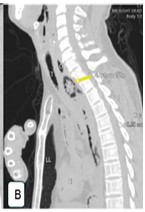

Boerhaave syndrome (BS) is a rare, life-threatening condition characterized by spontaneous esophageal rupture, commonly triggered by forceful vomiting. Due to its nonspecific presentation, BS is often misdiagnosed, leading to delayed intervention and high mortality. We report a case of BS presenting with hematemesis, respiratory distress, and collapse, emphasizing the forensic implications and the role of postmortem computed tomography (PMCT) in virtual autopsy. A 46-year-old male with a history of alcohol consumption experienced sudden-onset hematemesis and respiratory distress, followed by cardiopulmonary arrest. Despite resuscitation efforts, the patient was pronounced dead. Autopsy findings revealed a full-thickness esophageal rupture with mediastinal contamination and pleural effusions, confirming BS as the cause of death. PMCT successfully detected pneumomediastinum, free intrathoracic air, and mediastinal fluid, demonstrating its utility in forensic investigations. The case highlights key differential diagnoses of sudden death, including acute myocardial infarction, pulmonary embolism, and aortic dissection. This case aligns with existing literature where hematemesis, though less commonly reported, was a significant symptom preceding cardiovascular collapse. Delayed diagnosis of BS remains a critical factor contributing to poor outcomes and increased mortality rates. The integration of PMCT with conventional autopsy enhances the diagnostic accuracy of esophageal perforation-related deaths, particularly in forensic settings. Comparative analysis with previously reported cases underscores the need for heightened clinical suspicion and early imaging to prevent fatal outcomes. Boerhaave syndrome remains a diagnostic and therapeutic challenge, often leading to sudden and unexpected death. This case reinforces the medicolegal importance of virtual autopsy in identifying esophageal rupture, particularly in unwitnessed or unexplained deaths.